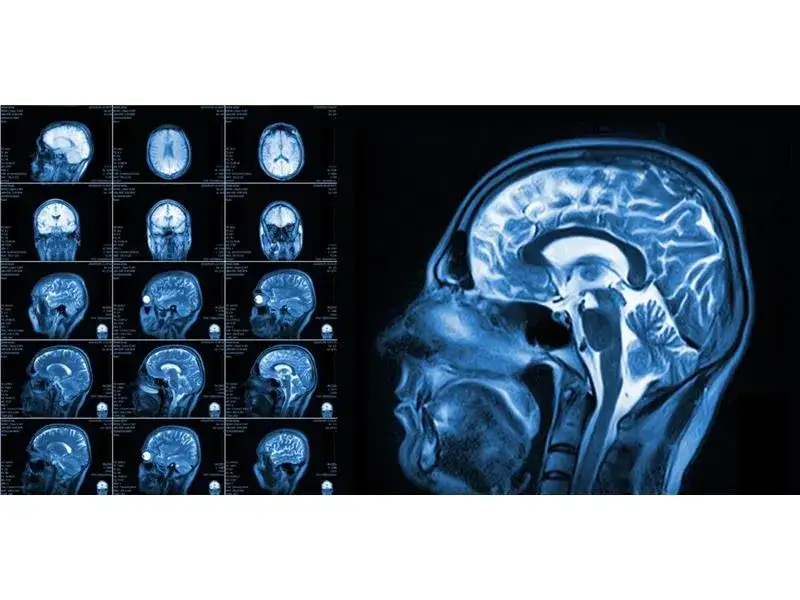

Rezonans magnetyczny (MRI) odgrywa kluczową rolę w rehabilitacji pacjentów, dostarczając szczegółowych informacji na temat stanu tkanek i narządów. To badanie obrazowe umożliwia lekarzom rehabilitacji dokładną ocenę urazów, chorób oraz zmian w organizmie, co jest niezbędne do skutecznego planowania terapii. Dzięki MRI, rehabilitanci mogą lepiej zrozumieć, jakie obszary wymagają interwencji oraz jakiego rodzaju ćwiczenia i terapie będą najskuteczniejsze.

W szczególności, rezonans magnetyczny jest niezwykle pomocny w diagnozowaniu schorzeń takich jak uszkodzenia więzadeł, dyskopatie czy zmiany zwyrodnieniowe stawów. Na przykład, pacjenci z urazami sportowymi często korzystają z MRI, aby zidentyfikować stopień uszkodzenia tkanek miękkich. Dzięki tym informacjom, lekarze mogą opracować spersonalizowane programy rehabilitacyjne, które przyspieszają proces powrotu do zdrowia.Co więcej, rezonans magnetyczny jest nieinwazyjnym badaniem, co oznacza, że pacjenci nie muszą się obawiać poważnych skutków ubocznych. To sprawia, że jest to idealne narzędzie diagnostyczne dla osób w różnym wieku, w tym seniorów, którzy mogą mieć inne schorzenia towarzyszące. W kontekście rehabilitacji, MRI nie tylko ułatwia diagnozę, ale także monitoruje postępy leczenia, co jest kluczowe dla efektywności terapii.